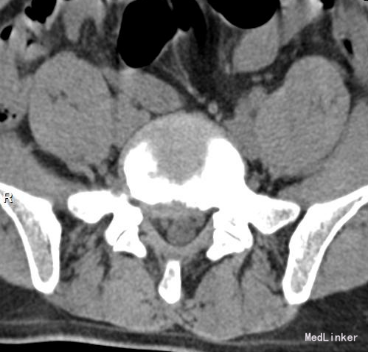

35岁 男性 主诉:反复右下肢放射性疼痛麻木8个月,加重3天

生命体征平稳,痛苦表情, 专科查体: 右下肢强迫性屈髋屈膝位; L5/S1棘突间及右侧椎旁压痛,并向右下肢放射; 右小腿后侧及足背外侧皮肤感觉减弱; 右足拇跖屈肌力3级; 右侧直腿抬高试验5°(+), 右侧跟腱反射消失。 入院三大常规,生化指标等均正常范围

诊断:腰椎间盘突出症 (腰5/骶1髓核游离型) VAS评分:9分 ODI评分:96% 疼痛剧烈,右下肢难以伸直,坐卧不宁;给予常规脱水,激素,止痛等治疗无效;不同意手术,反复要求保守治疗。 保守治疗3天,患者疼痛仍无明显缓解,同意行手术治疗 手术方案:椎板间隙入路PELD 术后予以止痛,脱水,小剂量激素等治疗, 术后第二天:右下肢麻木疼痛明显缓解。查体:右小腿后侧及足背外侧皮肤触觉恢复;右足拇跖屈肌力4+级;右侧直腿抬高试验(-);右侧跟腱反射仍减弱。 术后第5天:出现右小腿及足底针刺样疼痛症状加重,麻木感,伴有右下肢间歇性抽搐,次数较频繁,以夜间为甚。查体:腰椎活动无明显受限,右小腿后面及右足背外侧触痛明显;双下肢屈伸肌力、肌张力基本正常;右侧直腿抬高试验(-),右侧跟腱反射仍减弱。 予以加大NSAID及地米治疗,效果不明显,夜间疼痛难以入睡。复查腰椎MRI,未见髓核再脱出,减压彻底 诊断:考虑右侧骶1神经根神经病理性疼痛 治疗: 普瑞巴林 75mg Bid;神经妥乐平 2# Bid; 阿米替林 25mg Bid 外加神经营养治疗 治疗1周后,症状明显缓解